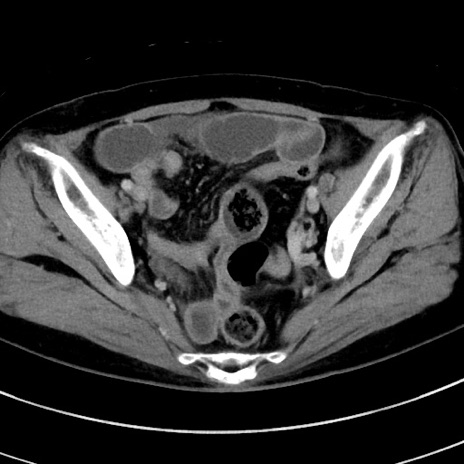

症例9(横断像)

【症例】 60歳代女性

【主訴】むかつき、みぞおちの痛み

【現病歴】3日前よりむかつきがあり、食事がとれない。

【既往歴】糖尿病

【身体所見】発熱なし、心窩部圧痛軽度あるも、腹膜刺激症状なし。

【データ】WBC 7400、CRP 1.92